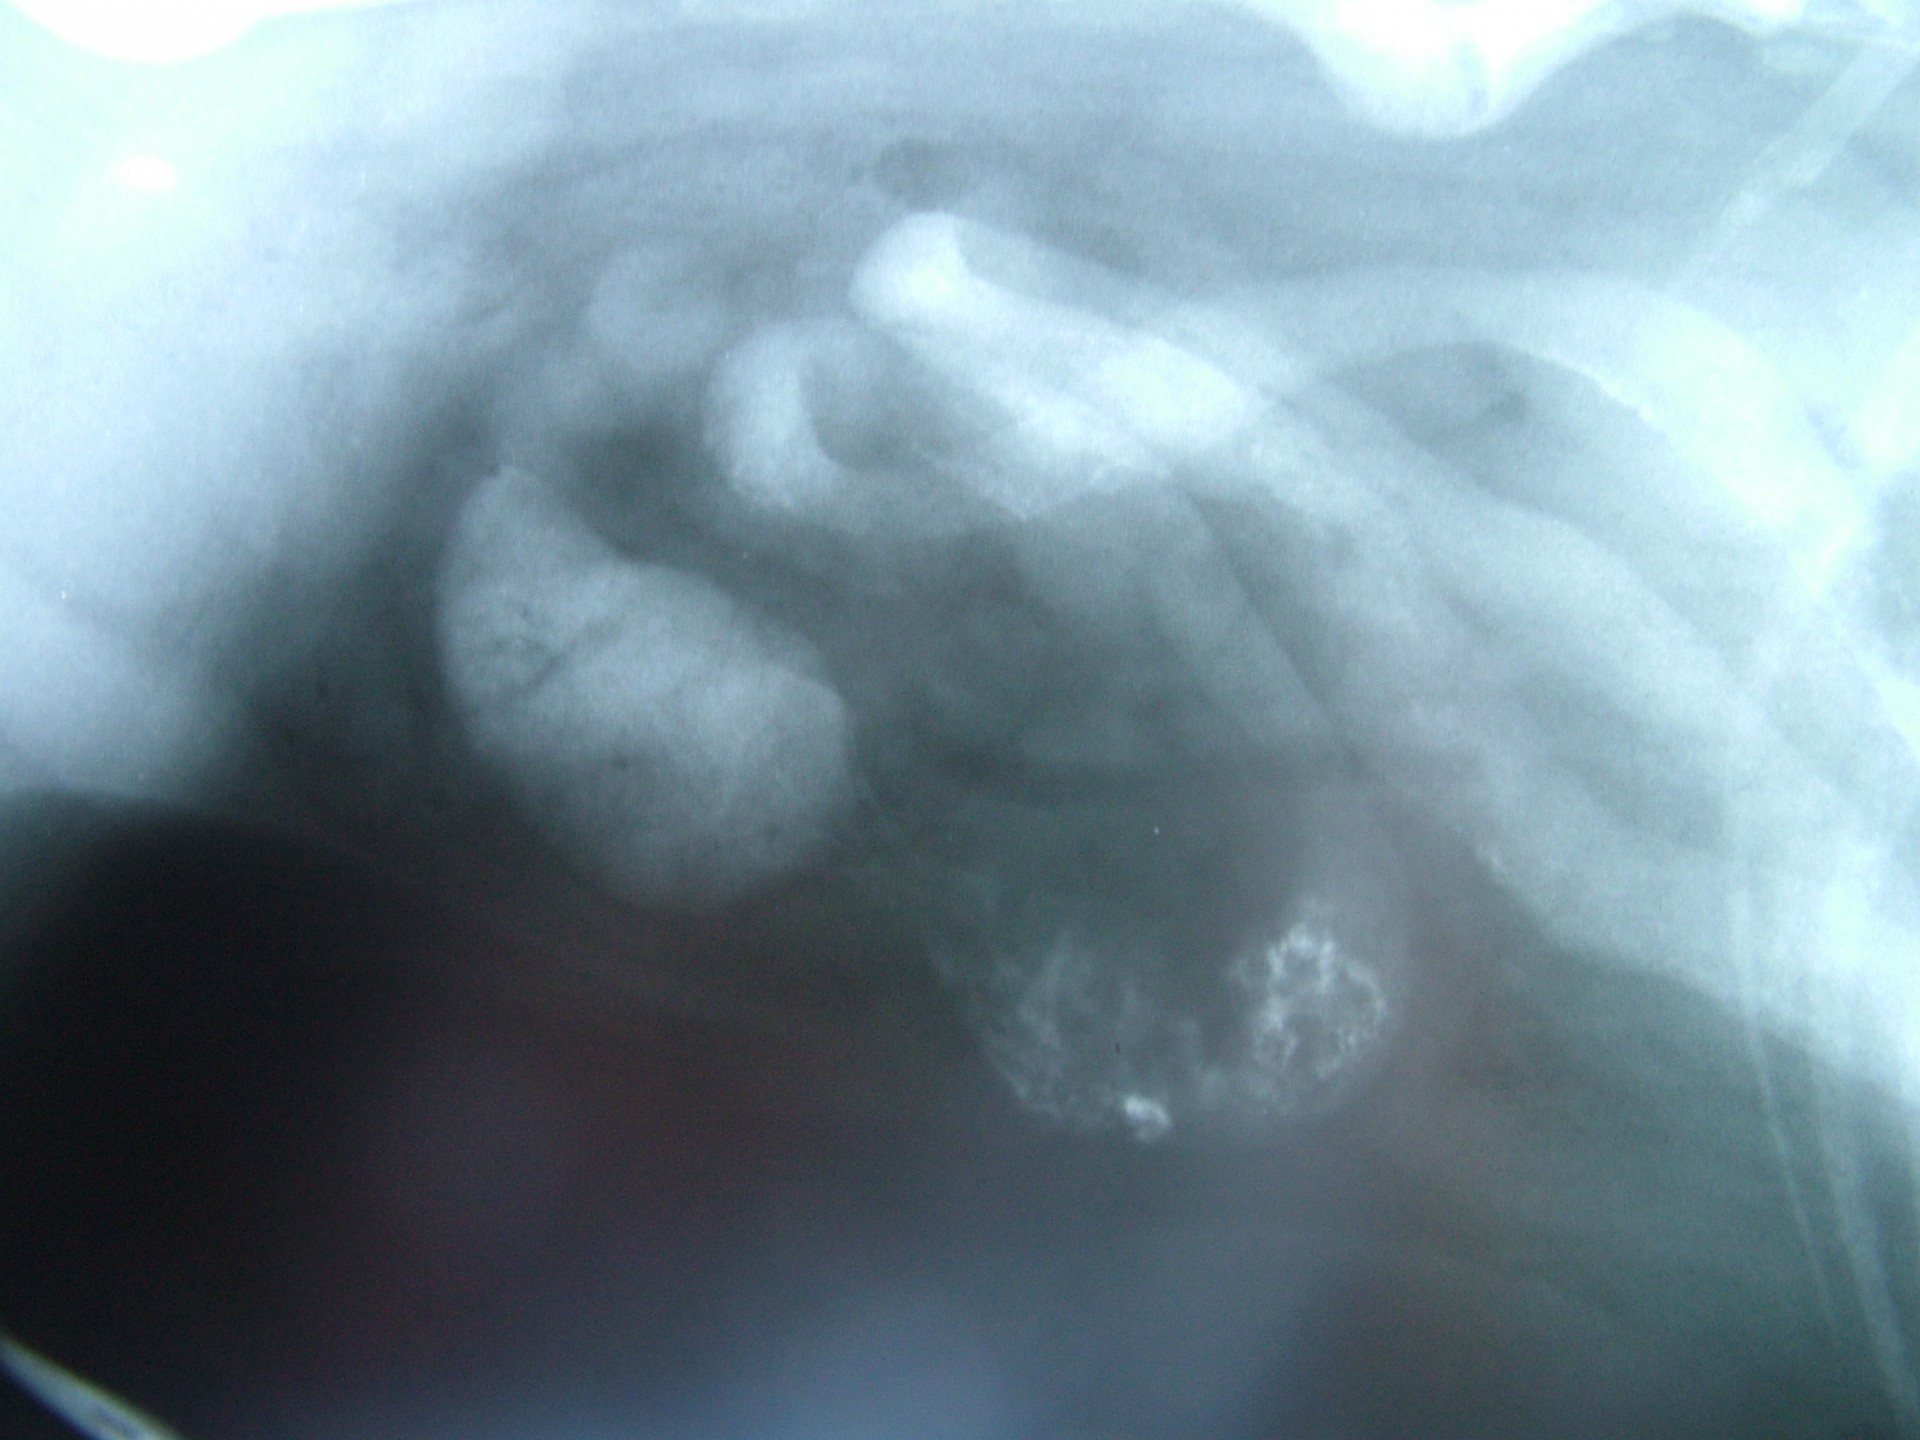

• Az un.: invaginációs ileus általában fiatal állatokban alakul ki. A bélelzáródás oka ebben az esetben, hogy a bélmozgások jelentős felgyorsulása következtében ( bélgyulladás, hasmenés ) egy bélszakasz a mögötte lévő bélszakaszba türemkedik, ezáltal annak lumenét elzárja.

A különféle bélelzáródások diagnosztikája során a kórelőzmény (pl.: játék lenyelése) és a klinikai tünetek (hányás, a has feszítése, tapintható idegentest a hasüregben stb.) mellett kiegészítő vizsgálatként RTG vizsgálat és a hasüreg ultrahangos vizsgálata jöhet szóba. A bél elzáródását okozó képletek az esetek döntő többségében nem adnak röntgen árnyékot, ezért un.: röntgen kontrasztanyagot etetünk az állattal és többszöri röntgenfelvétel készítésével figyeljük a tovahaladását.

Abban az esetben, ha a kontraszt anyag elakad, az ileus diagnózisa nagy biztonsággal kimondható. Ultrahangos vizsgálattal a bélelzáródás előtti területen felhalmozódó béltartalom un.: inga-mozgása is egyértelműen bélelzáródásra utaló diagnosztikai jel.